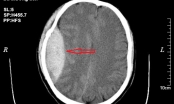

Bệnh viện Quốc tế City (TP HCM) vừa phẫu thuật thành công cho bé gái N.G.V (2 tuổi, quê Đà Nẵng) bị u mạch máu não thùy thái dương bằng hệ thống máy định vị 3D navigation kết hợp kính hiển vi.

Trước đó, bé được chuyển tới bệnh viện với chẩn đoán u mạch máu não thùy thái dương trái. Theo chia sẻ của chị L. - mẹ bé G.V, trước khi phát hiện khối u mạch máu não, bé sinh hoạt phát triển bình thường như bao trẻ khác. Khi đang chạy nhảy nô đùa, bé đột nhiên nôn mửa, người tê liệt, co giật.

Gia đình đưa vào bệnh viện tại Đà Nẵng cấp cứu. Kết quả chụp CT cho thấy, bé bị khối u ở mạch máu não. Sau đó, gia đình quyết định đưa bé vào TP HCM để phẫu thuật.

Sau khi kiểm tra lâm sàng, cận lâm sàng và điều trị viêm phổi ổn định, bé G.V được chỉ định phẫu thuật. Ê-kíp bác sĩ Khoa Ngoại thần kinh Bệnh viện Quốc tế City tiến hành phẫu thuật cho bé bằng công nghệ cao: sử dụng hệ thống máy định vị 3D navigation kết hợp kính hiển vi.

Đến 11h15 cùng ngày, ca phẫu thuật thành công, bé được chuyển về Khoa Chăm sóc tích cực để theo dõi hậu phẫu.

Bác sĩ cho hay, trường hợp trẻ mắc chứng u mạch máu não thì xuất hiện chứng đau đầu, nôn mửa. Đây là triệu chứng khá điển hình của u mạch máu não, song thường bị chẩn đoán nhầm là bệnh đường ruột và bệnh dạ dày.